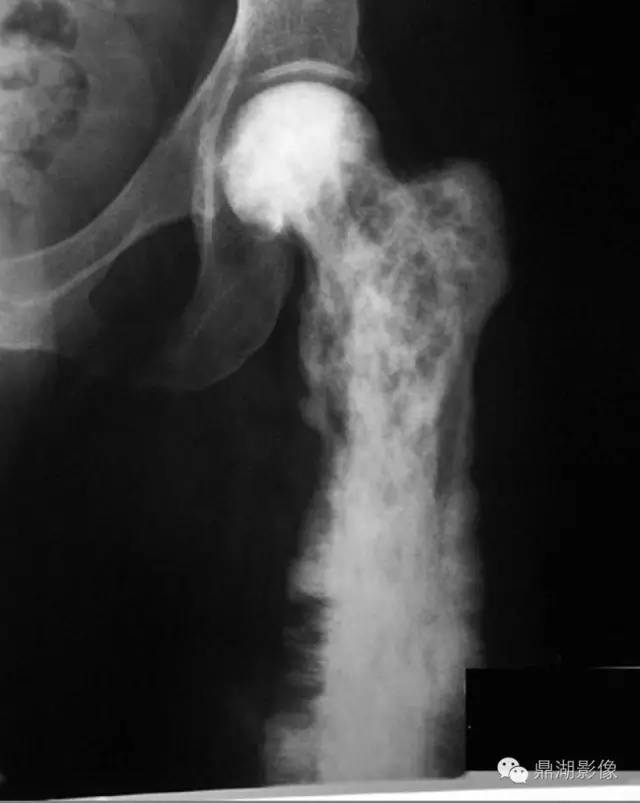

佩吉特骨病常单发也可多发,可累及全身任何骨骼,最常受累的骨骼包括颅骨、脊柱、骨盆及下肢,尤其是股骨近端。

佩吉特骨病的主要症状是疼痛,受累的长骨的骨皮质可增厚、骨干增粗,渐进或者有时出现严重的畸形,随即出现关节炎、在病变骨的凸面出现应力性骨折(尤其是股骨发生的粉笔棒断裂,chalk stick fracture)以及明显的病理性骨折。

X线可表现出病变处皮质增厚、骨增粗、溶骨和骨硬化同时存在的现象、粗糙的骨小梁等。长骨受累及早期可由一端的软骨下骨开始发病,延伸至骨干的不同部位,出现病变与正常结构的分界,如V形裂解区(“火焰”或“割草刀片”影像学改变)。负重部位的骨骼则可出现弯曲及骨皮质出现小的裂隙骨折,尤其是股骨病变时凸面的病理性骨折明显。

佩吉特骨病恶变时可出现溶骨性改变加重、骨皮质遭到破坏、软组织肿块影。核素骨扫描有助于评估病变范围及治疗的效果但病变晚期时病灶核素摄取率会降低,佩吉特病恶变时也可出现核素低摄取区。